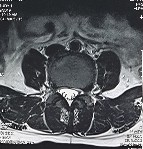

2. Hình ảnh khảo sát dẫn truyền thần kinh, điện cơ đồ và MRI (thực hiện trên mẫu nghiên cứu: bệnh nhân Hoàng Đình H., mã số bệnh nhân 1010320).

Bệnh nhân H., khi khám lâm sàng có biểu hiện tổn thương rễ thần kinh L4, L5, S1. Kết quả xét nghiệm điện cơ thấy: dẫn truyền thần kinh thấy mất phản xạ H, nhưng kết quả khi điện cơ kim có biểu hiện tổn thương rễ thần kinh L5 . Kết quả chụp cộng hưởng từ là tổn thương thoát vị L4 – L5, L5 – S1. Như vậy, trên bệnh nhân này vị trí tổn thương thực tế khi kết hợp phối hợp giữa khám lâm sàng, chẩn đoán hình ảnh và chẩn đoán chức năng là vị trí rễ thần kinh L5.

Hình ảnh thoát vị đĩa đệm trên phim chụp MRI.